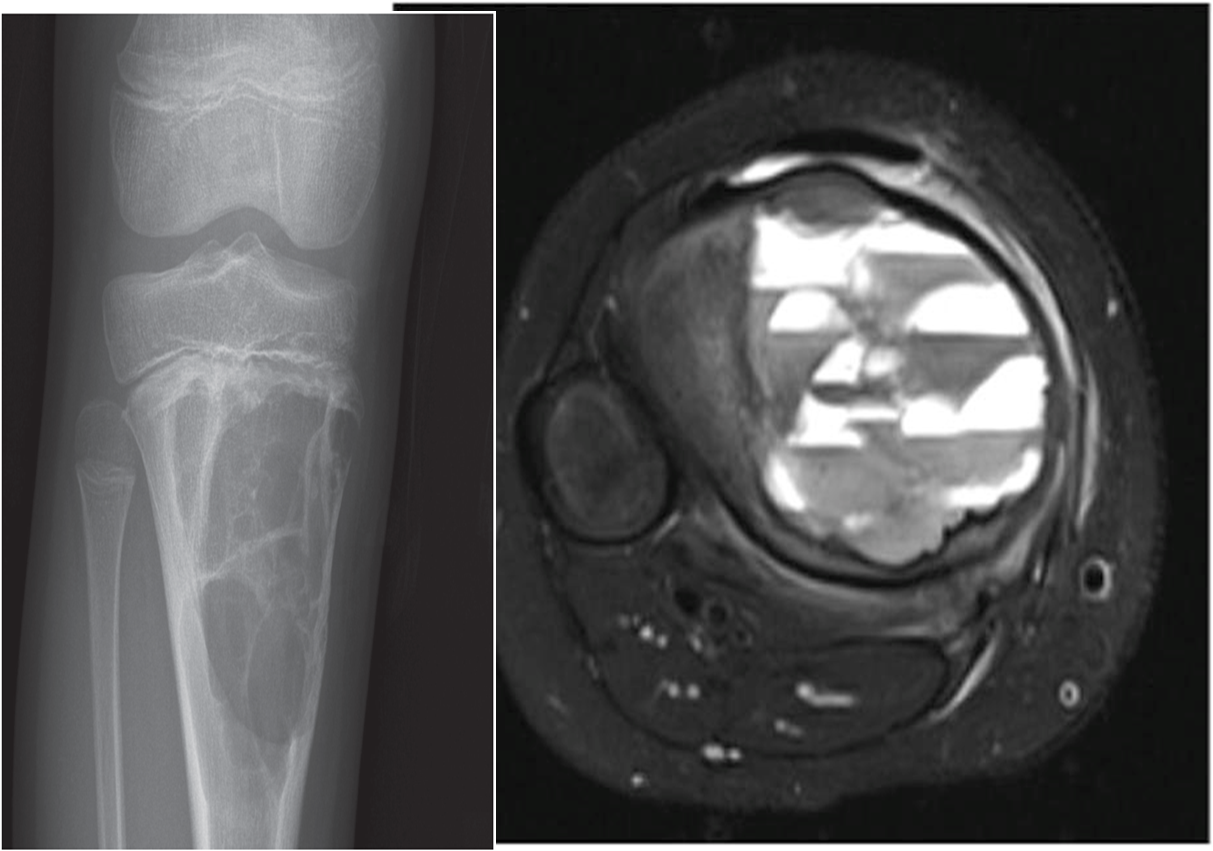

14 years old patient has lower leg pain. X-ray Knee is requested

Within the metaphysis, doesn’t extent to the epiphysis

- •Geographical

- •X ray: expansile lytic lesion , cortex is thinned out

- •MR : fluid level

- •Cause: aneurysmal bone cyst (age, location, appearance)

X-ray shows: Lytic expansile lesion located on the metaphysis(benign). MRI show fluid levels in the lesion